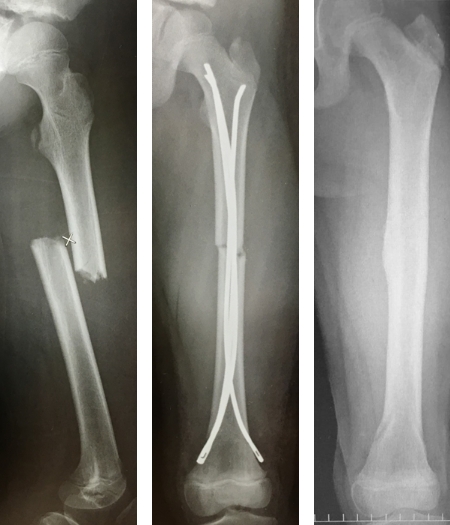

(2)学童期の大腿骨/脛骨骨幹部骨折:治療の多くは非観血的治療ですが、転位を伴った場合には観血的治療が望ましい症例もあります(図7)。早期の復学を目指す手術方法として有効で術後早期に自動運動が可能であり、入院期間を短くし家族の負担も減らせます。Ender釘は骨端線を避けて挿入することが可能であり、長さや径も豊富です。

図7 学童期の大腿骨骨幹部骨折に対するEnder髄内釘固定術